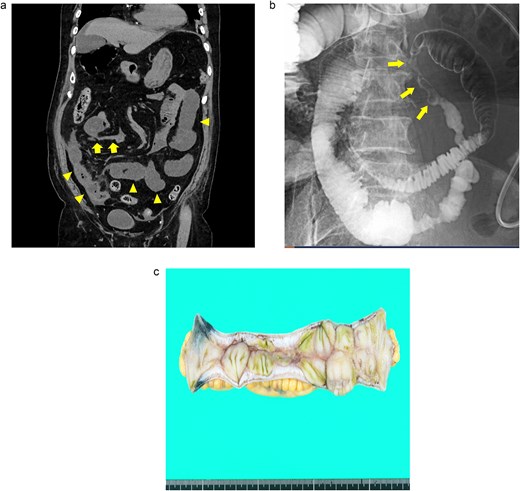

An 88-year-old woman presented with recurrent episodes of epigastric pain. Three months prior, she experienced similar abdominal pain, and CT revealed HPVG and mesenteric emphysema without mesenteric ischemia or bowel strictures. The patient’s symptoms resolved with conservative treatment, and none of the CT features remained by the follow-up. Her vital signs were stable, and most of the laboratory test results were normal, including WBC count (6700/μl), CRP concentration (0.95 mg/dl), Hb level (12.3 g/dl), and Lac concentration (0.9 mmol/L). However, her blood glucose level (BGL) was elevated (315 mg/dl), as was her glycated hemoglobin (HbA1c) level (9.0%). Contrast-enhanced CT revealed a segmental luminal stricture with wall thickening in the distal ileum, suggestive of bowel obstruction (Fig. 2a). A long intestinal tube was placed for luminal decompression, and fluoroscopy confirmed the presence of segmental, smooth luminal narrowing in the distal ileum (Fig. 2b).

Case 2: (a) Contrast-enhanced CT of the abdomen. The arrowheads indicate segmental luminal stricture with wall thickening in the distal ileum. (b) Fluoroscopy with a long intestinal tube. The arrows indicate a segmental, smooth luminal narrowing in the distal ileum. (c) Macroscopic view of the resected specimen. Circumferential ulceration and surrounding fibrosis are visible in line with the stenotic site.

Exploratory laparoscopy revealed an 8-cm-long bowel stricture with segmental induration 30 cm from the ileocecal valve, which was resected. The pathological specimen revealed circumferential ulcer formation at the stenotic site, accompanied by granulocyte infiltration and fibrosis extending from the submucosa through the proper muscle layer. No signs of tumors or IBD were noted (Fig. 2c). The postoperative course was uneventful, and she was discharged on the eighth postoperative day. By the 16-month follow-up, she had not had any recurrences of abdominal symptoms.